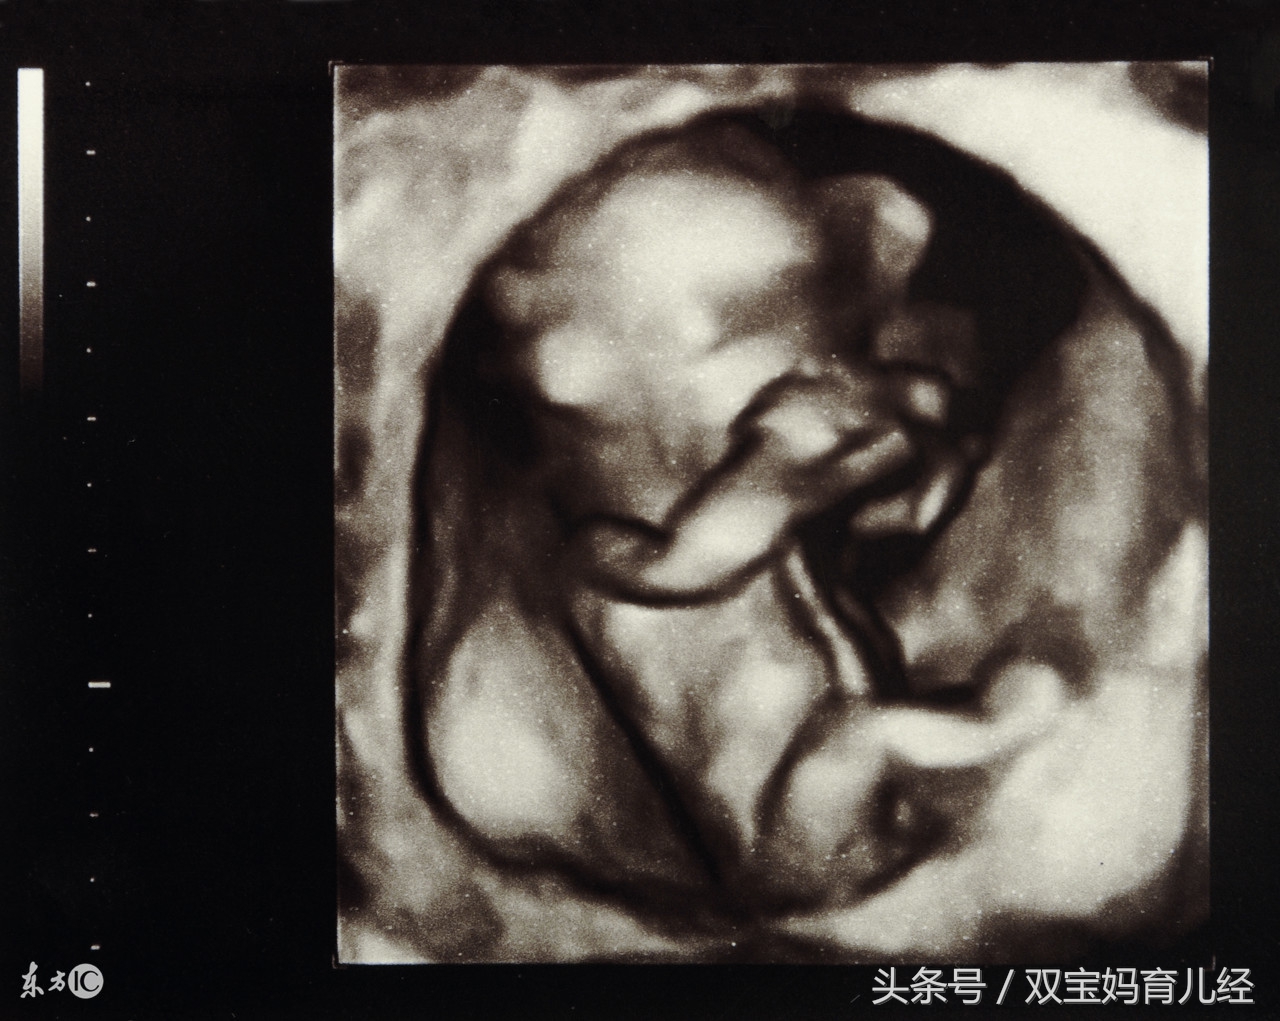

到了医院,医生马上安排了B超检查,惊奇地发现肚子里的宝宝一只脚已经伸到了子宫外!孕周增大,肚子里的宝宝活动太频繁,一脚把玲姐的子宫给踢破了!

医生解释,因为玲姐第一胎是剖腹产,子宫动过手术,属于疤痕子宫.在疤痕没有完全愈合的情况下,又匆匆忙忙怀上了第二胎,子宫根本没有得到休息, 到了孕晚期,就容易发生宝宝在肚子里面施展不开,踢破妈妈子宫,导致子宫破裂的情况.

在孕22~25周进行系统B超检查时就应明确胎盘位置及其与瘢痕的关系,对可疑患者应于孕28~30周复查胎盘位置,超声多普勒检查是否有胎盘植入,必要时行MRI检查进一步明确诊断,并注意无痛性阴道流血情况。

从孕34周开始,应每周进行B超监测子宫下段的肌层变化,怀孕38周的时候就要住院监测子宫下段肌层厚度的变化。